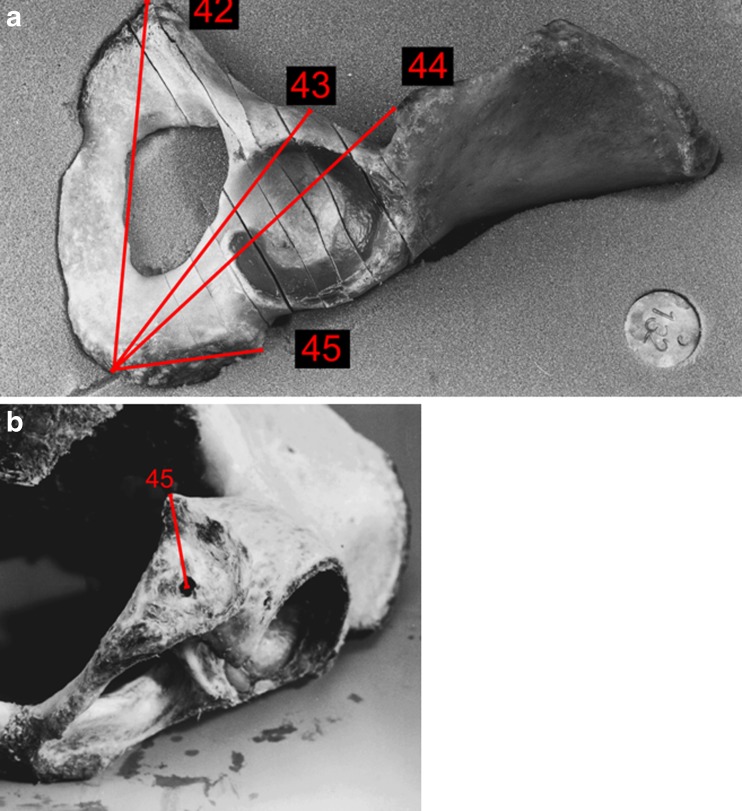

Fig. 4.

Specimen with antegrade entry point of posterior column screw. Distances to the different bony landmarks are marked in straight lines. Numbers are for identification use

Fig. 5.

a, b Specimen with retrograde entry point of posterior column screw. Distances to the different bony landmarks are marked in straight lines. Numbers are for identification use

There were no gender differences in measurements around the antegrade entry point of the posterior column screw (Table 3). The mean distance to the ischial spine, linea terminalis and anterior inferior iliac spine was similar in both sexes. In the retrograde approach (Table 4), distances to the iliopectineal eminence and anterior inferior iliac spine were different between genders (p = 0.003 and p = 0.006, respectively).

Table 3.

Distance of screw entry point to various landmarks. Identification number in brackets (see Fig. 4)

| Distance of antegrade entry point posterior column screw to various landmarks | Male specimen | Female specimen | P value |

|---|---|---|---|

| Mean [cm; (range) standard deviation] | |||

| Anterior superior iliac spine (33)a | 7.4 (6.6–8.9) 0.86 | 7.3 (6.1–8.0) 0.62 | 0.830 |

| Anterior inferior iliac spine (34)a | 5.3 (5.0–5.6) 0.22 | 5.3 (4.0–6.1) 0.75 | 0.519 |

| Iliopectineal eminence (35)a | 5.1 (3.9–6.3) 0.97 | 5.7 (3.5–7.8) 1.48 | 0.390 |

| Ischial spine (36)a | 8.0 (6.2–10.1) 1.38 | 8.0 (6.9–9.5) 0.93 | 0.886 |

| Sacroiliac joint on height linea terminalis (37)a | 3.5 (3.0–4.2) 0.49 | 3.2 (2.1–4.5) 0.76 | 0.281 |

| Linea terminalis (56)a | 1.5 (0.8–3.4) 0.99 | 1.5 (0.5–2.5) 0.86 | 0.885 |

asee Fig. 4

Table 4.

Distance of screw entry point to various landmarks. Identification number in brackets (see Fig. 5a,b)

| Distance of retrograde entry point posterior column screw to various landmarks | Male specimen | Female specimen | P value |

| Centre of symphysis (42)a | 12.7 (11.6–13.4) 0.74 | 12.0 (11.5–12.4) 0.36 | 0.073 |

| Iliopectineal eminence (43)a | 11.5 (10.9–12.0) 0.42 | 9.8 (9.3–10.4) 0.42 | 0.003 |

| Anterior inferior iliac spine (44)a | 13.7 (12.8–14.3) 0.54 | 12.1 (11.2–13.6) 0.75 | 0.006 |

| Ischial tuberosity (45)a | 2.6 (1.5–3.3) 0.71 | 2.7 (1.1–4.1) 1.09 | 0.830 |

asee Fig. 5a, b